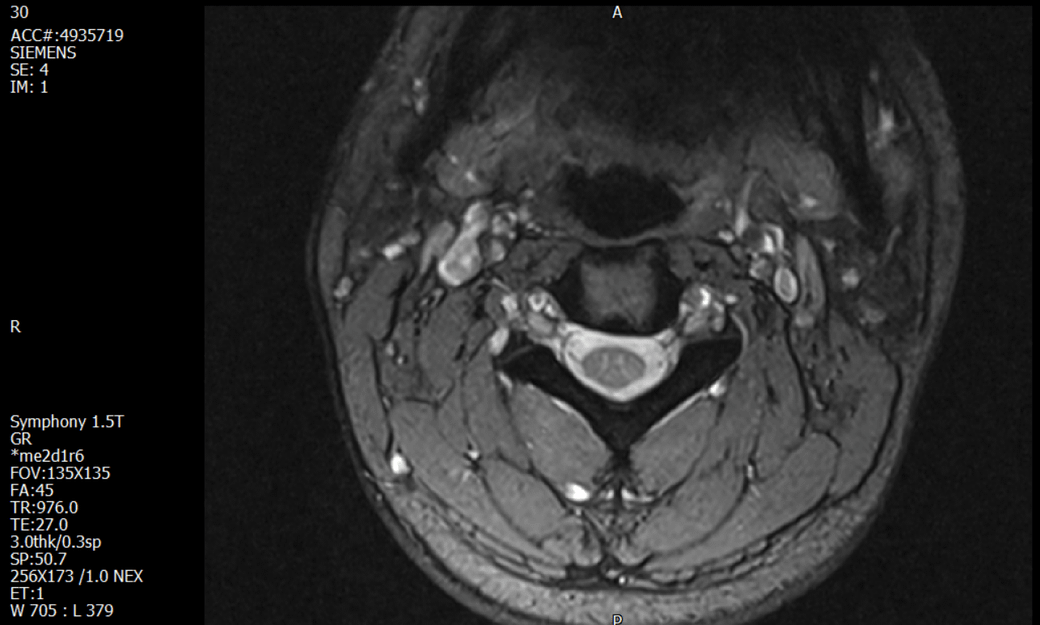

경추 요추 디스크 MRI판독 부탁드립니다.

- 3개월전 좌측 상지 저림(힘빠짐) 발생. 이틀뒤 에 좌측 하지 저림(힘빠짐) 발생.

-11월, 증상발생 직후 잠실소재 척추전문병원 MRI 요추경추 촬영 후 신경외과 박사 진료, 허리는 매우 건강, 경추는 퇴행성 진행되고 있지만 디스크라고 보기 어려움. 신경막만 살짝 건드리는 정도고 이 정도로 힘빠짐이나 저림이 오지 않고 원인은 다른 곳에 있을 가능성.

1. MRI 상 , 경추와 요추에 디스크가 있나요? 있다면 좌측 팔과 다리에 저림 및 힘빠짐을 줄 정도인가요?

• 1번 째 사진

• 1. MRI 사진을 보았을 때 디스크를 의심해볼 수 있는 소견이 살짝살짝 보이긴 합니다만, 상하지의 저림 및 힘빠짐을 유발할 정도인지는 솔직히 회의적입니다.

4. 말씀하신 것처럼 특히 요추부 MRI는 디스크를 찾기 어렵습니다.